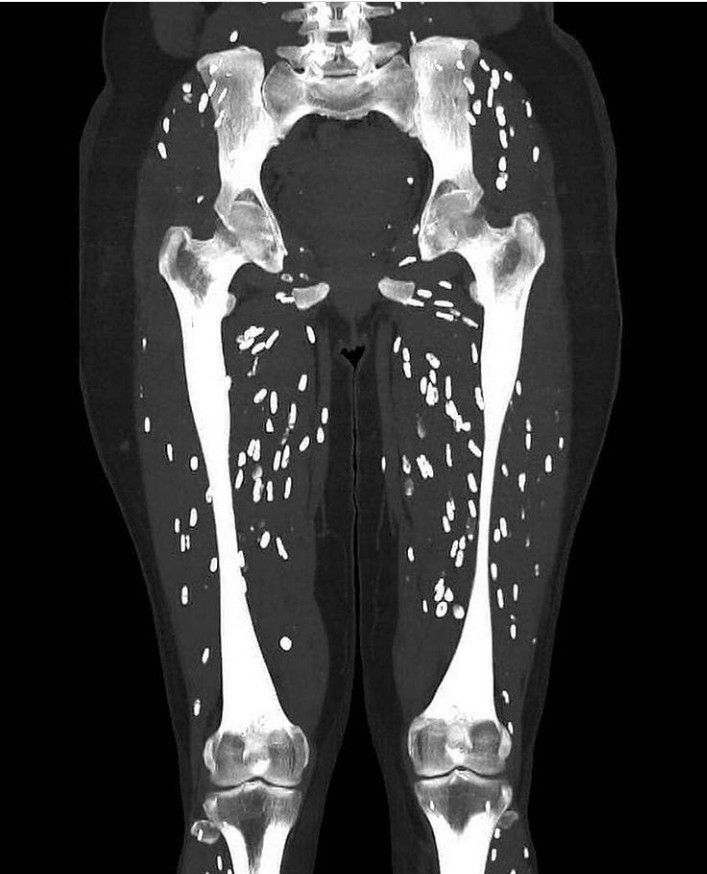

This CT scan of the cysticercosis patient shows: >Ovoid flecks of calcification resembling the grains of rice in the soft tissue of lower extremities. > As it can be seen that the calcifications are parallel to the long axis of the muscle. This is the characteristic feature of infection with Taenia solium. >When the host detects this pathogen, it causes an inflammatory response and kills the larval cysts (cysticerci) which undergoes granulomatous change and become calcified. Case study by: https://www.instagram.com/p/CPI0Q4ChlxK/?utm_medium=copy_link